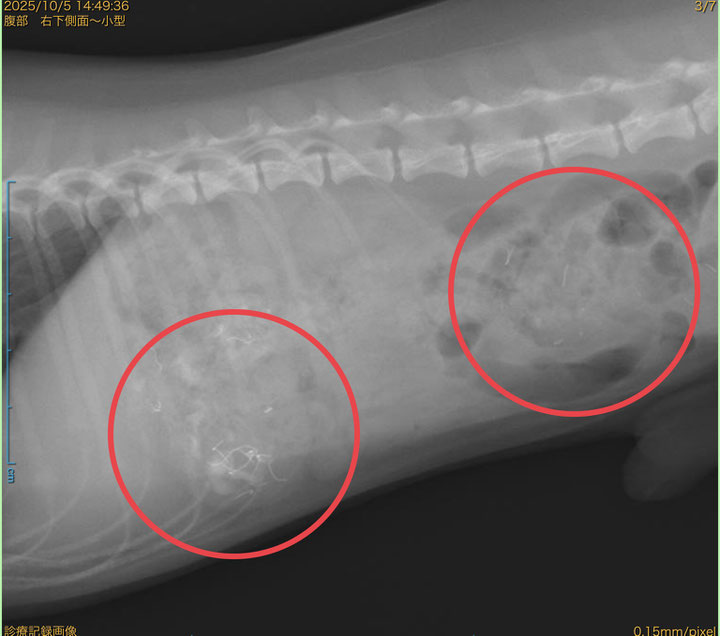

今回のレントゲン写真は、犬が電気コードをかじって銅線を誤食した症例です。

レントゲンでは、胃や腸の中に白く写る金属線の影が確認されることがあります。

診断には、レントゲン検査やエコー検査を行います。

金属はレントゲンで白く映るため、位置や量を確認して治療方針を決めます。